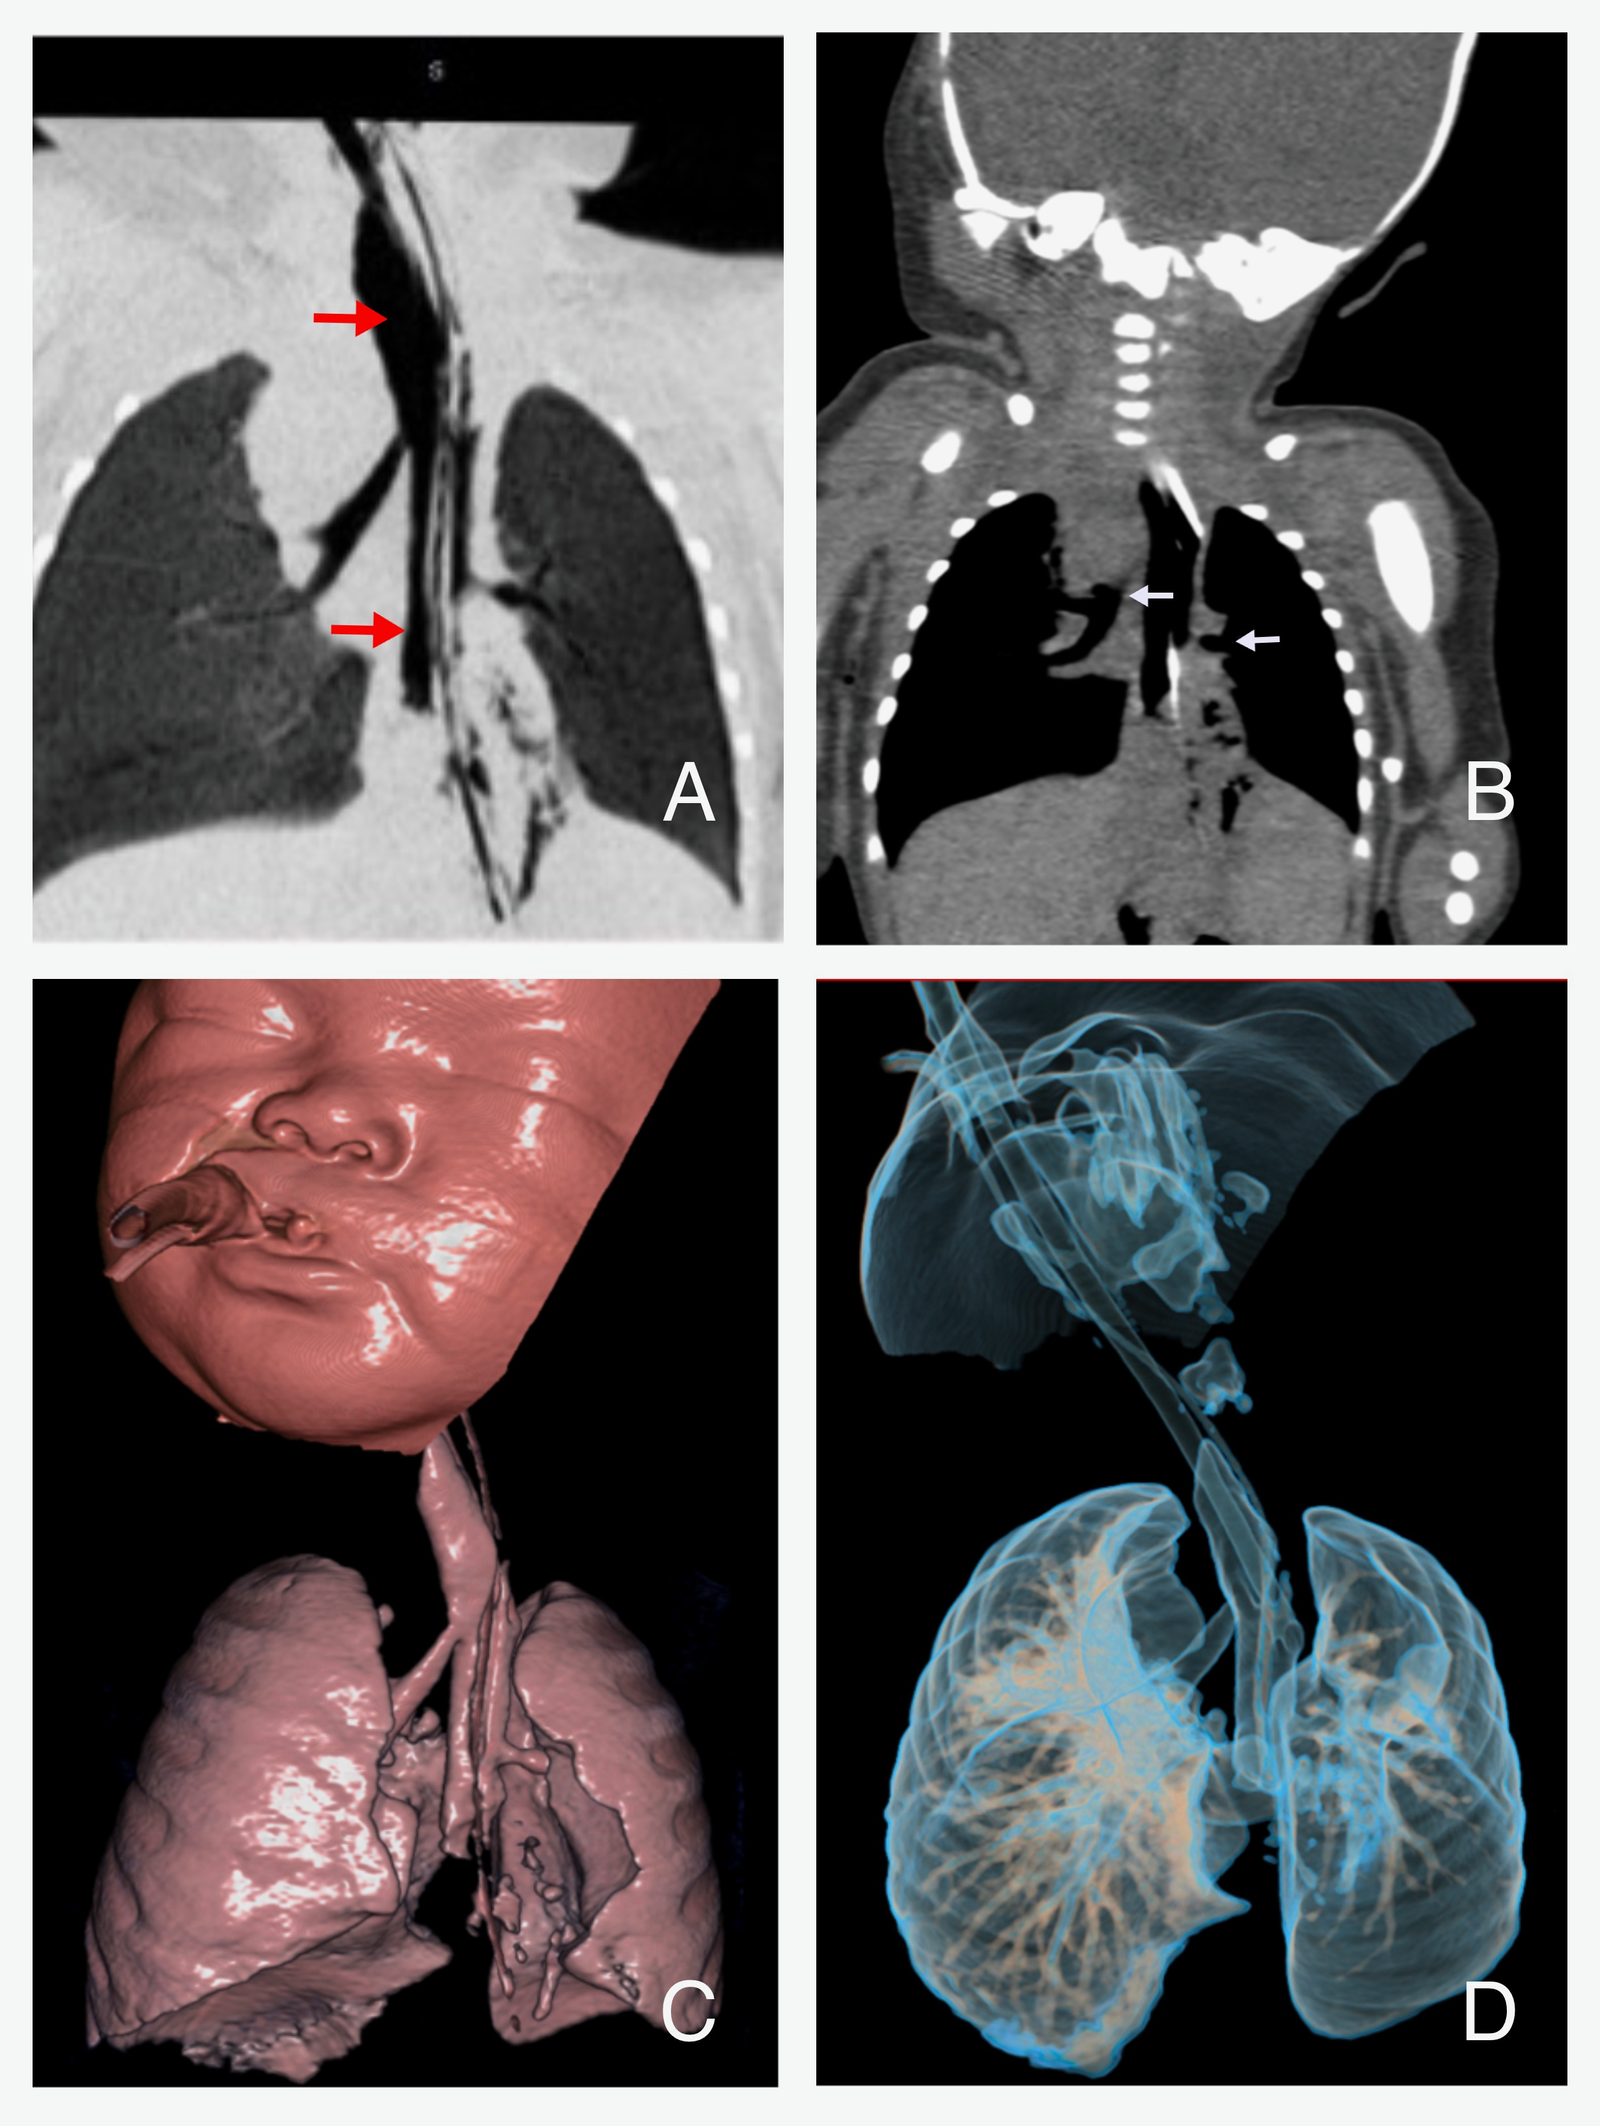

On day four, a plain CT scan of the neck and chest, with 3D airway reconstruction, and abdomen was performed (Figure 4.). It confirmed abnormal airway anatomy consistent with Type III TA: both main bronchi arose from the esophagus, which terminated in a hiatal hernia. The left lung was hypoplastic, likely due to the absence of lower lobar structures, while the right lung appeared normally formed but showed posterior segment consolidation, consistent with aspiration. The liver, spleen, kidneys, urinary bladder and dorsal spine were unremarkable. Genetic consultation was obtained, and chromosomal analysis was performed, which revealed a karyotype of 46, XX in 5 metaphase spread and was negative for trisomy 13, 18, and 21.

CT and 3D reconstructions of airway

Figure 4. Coronal chest CT and 3D reconstructions showing right and left main bronchi originating from an air-filled column continuous with the esophagus without a distinct carina; ETT and OGT localized in a single air-filled column.